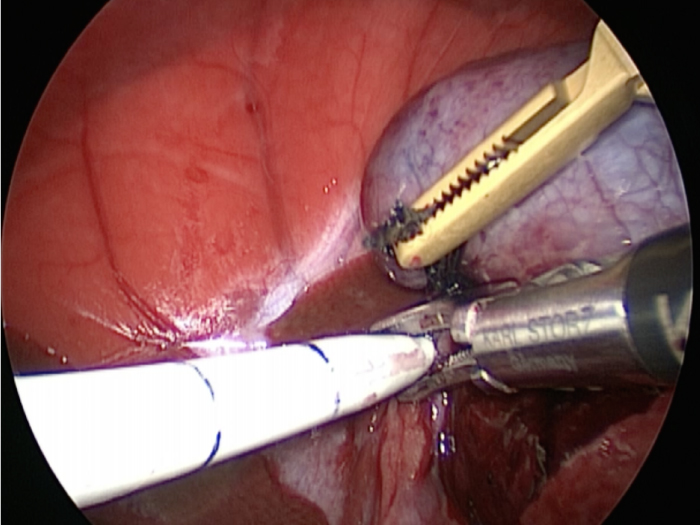

胆嚢の頸部に糸を通し動脈を確保しています。

総胆洗浄をして詰まりがないかまずは確認します。(右)

きれいに開通していました。鉗子が大きく感じますが体が小さいので大きく見えます。

胆嚢を少しずつ丁寧に肝臓から剥がしています。

回収袋にいれて体外に摘出していきます。

お腹の中を洗浄して終了となります。